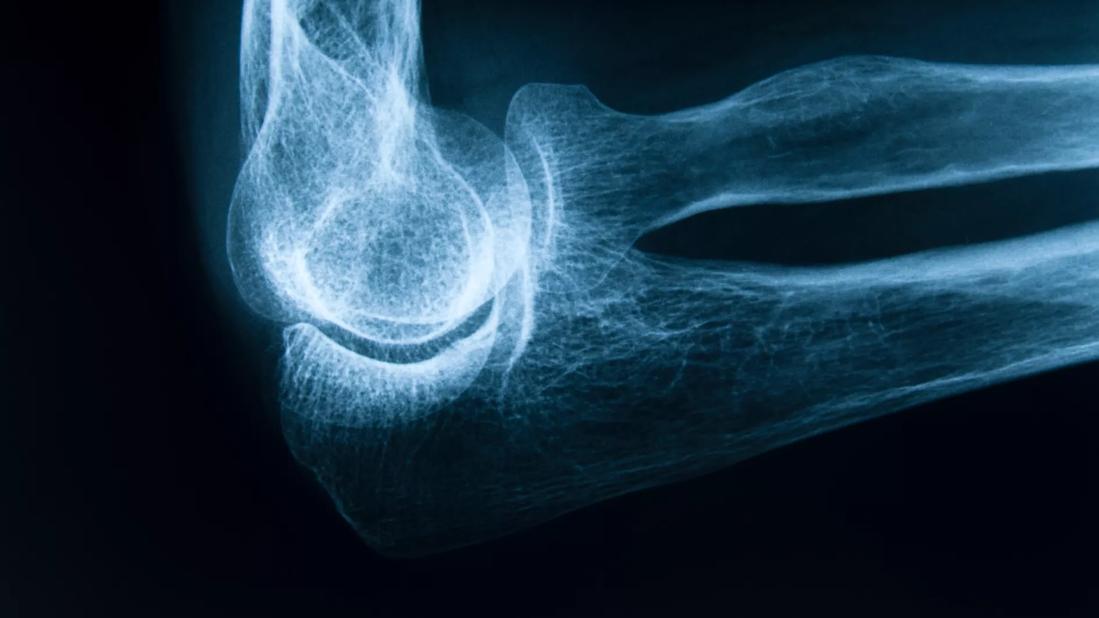

Postmenopausal Women and Osteoporosis Prevention: Which Medications to Use and When?

Up to 20 percent of bone loss occurs in women in their first five years of menopause. So it is imperative for physicians to discuss and institute a bone loss prevention plan when the first signs of menopause appear, says women’s health specialist Holly L. Thacker MD, FACP, Director, Cleveland Clinic Center for Specialized Women’s Health; Professor, Cleveland Clinic Lerner College of Medicine of Case Western Reserve University; and Executive Director of Speaking of Women’s Health.

Preventing fractures is critically important since hip fractures, for instance, significantly increase morbidity and mortality, and decrease quality of life in midlife women and beyond, and can lead to death or nursing home placement.